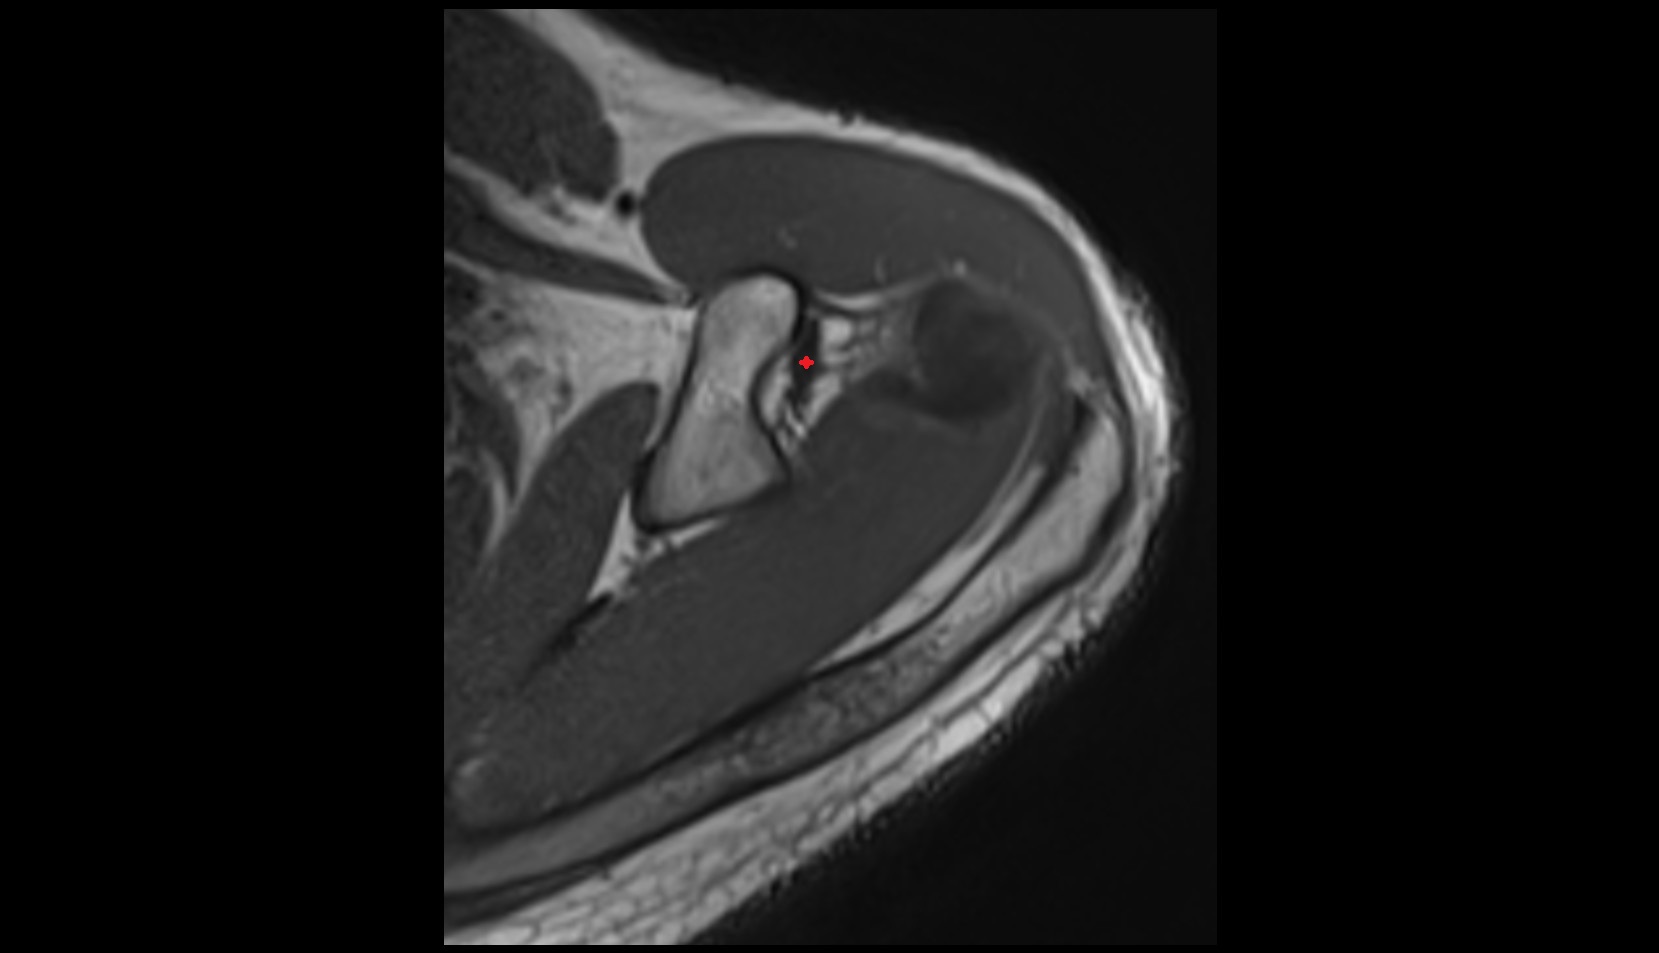

- Temporomandibular joint

- Articular disc of temporomandibular joint

- Mandibular condyle

- Mandibular fossa